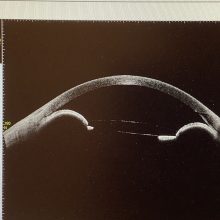

今日の外来では約5年前に両眼とも眼内レンズのズレで、そのズレたレンズを取り出し新たなレンズを眼の壁にレンズを固定する強膜内固定の手術を受けていただいた50歳代半ばの男性が、今朝から『左眼が痛くて、スクリーンがかかった見え方になってしまった』と急遽いらっしゃいました。この方は、時々、レンズの後ろに虹彩が引っかかってしまう“虹彩捕獲”という状態を起こしていたのですが、今回は虹彩が完全にレンズの後ろに回ってしまい瞳孔がレンズで塞がってしまう“逆瞳孔ブロック”という状態を起こしてしまっていました。“逆”というのは、通常の瞳孔ブロックというのは、閉塞隅角緑内障やぶどう膜炎などで虹彩と瞳孔がくっついてしまい眼の中の水の循環ができなくなってしまう状態ですが、この患者さんでは虹彩がレンズの後ろ側に回って起こる瞳孔ブロックなので“逆”がつきます。虹彩より後ろ(硝子体側)にある“毛様体”から眼の中の水(房水)が作られ、瞳孔を通って眼の前のスペース(前房)に回り、角膜と虹彩の付け根の“隅角”から房水は眼の外に流れていくのですが、瞳孔ブロックでも逆瞳孔ブロックでも、瞳孔が閉じてしまうと、房水は作られるのは続いても、瞳孔を通りにくくなり、硝子体の中に水がどんどん溜まり圧が上がることで、隅角が閉じて、余計に房水の排出が悪くなり眼圧がどんどん上がってしまうという悪循環を生じます。

この患者さんも眼圧が60mmHgを超え、眼がパンパンになってしまったため、眼が痛くなり、角膜が浮腫んで見え方も悪い状態となっていました。強膜内固定の手術の時に虹彩切除をしていれば、虹彩の前後で房水の流れができるため、このようなことにはならないのですが、この患者さんでは虹彩切除をしたいなかったので、レーザーで虹彩に穴を開けるレーザー虹彩切開術(LI)を行わないといけないかと思ったのですが、今回は瞳孔を開く点眼薬(散瞳薬)を使うことで、虹彩が眼内レンズの前方に戻り逆瞳孔ブロックが解除されたので、今日のところはレーザーの処置はせずに後日改めて行うこととさせていただきました。強膜内固定の時に虹彩切除をするかどうかは議論のあるところかとは思いますが、このようなケースを経験すると、しておいた方がよいかと思いました。